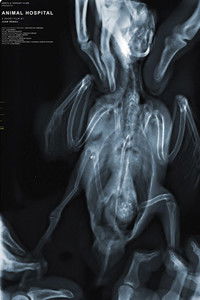

In a world where communication between humans and animals remains a mystery, a fundamental question arises—do animals suffer? People take their pets to Hospital Escuela in search of relief, while the future veterinarians learn and practice how to ease the animals’ pain.